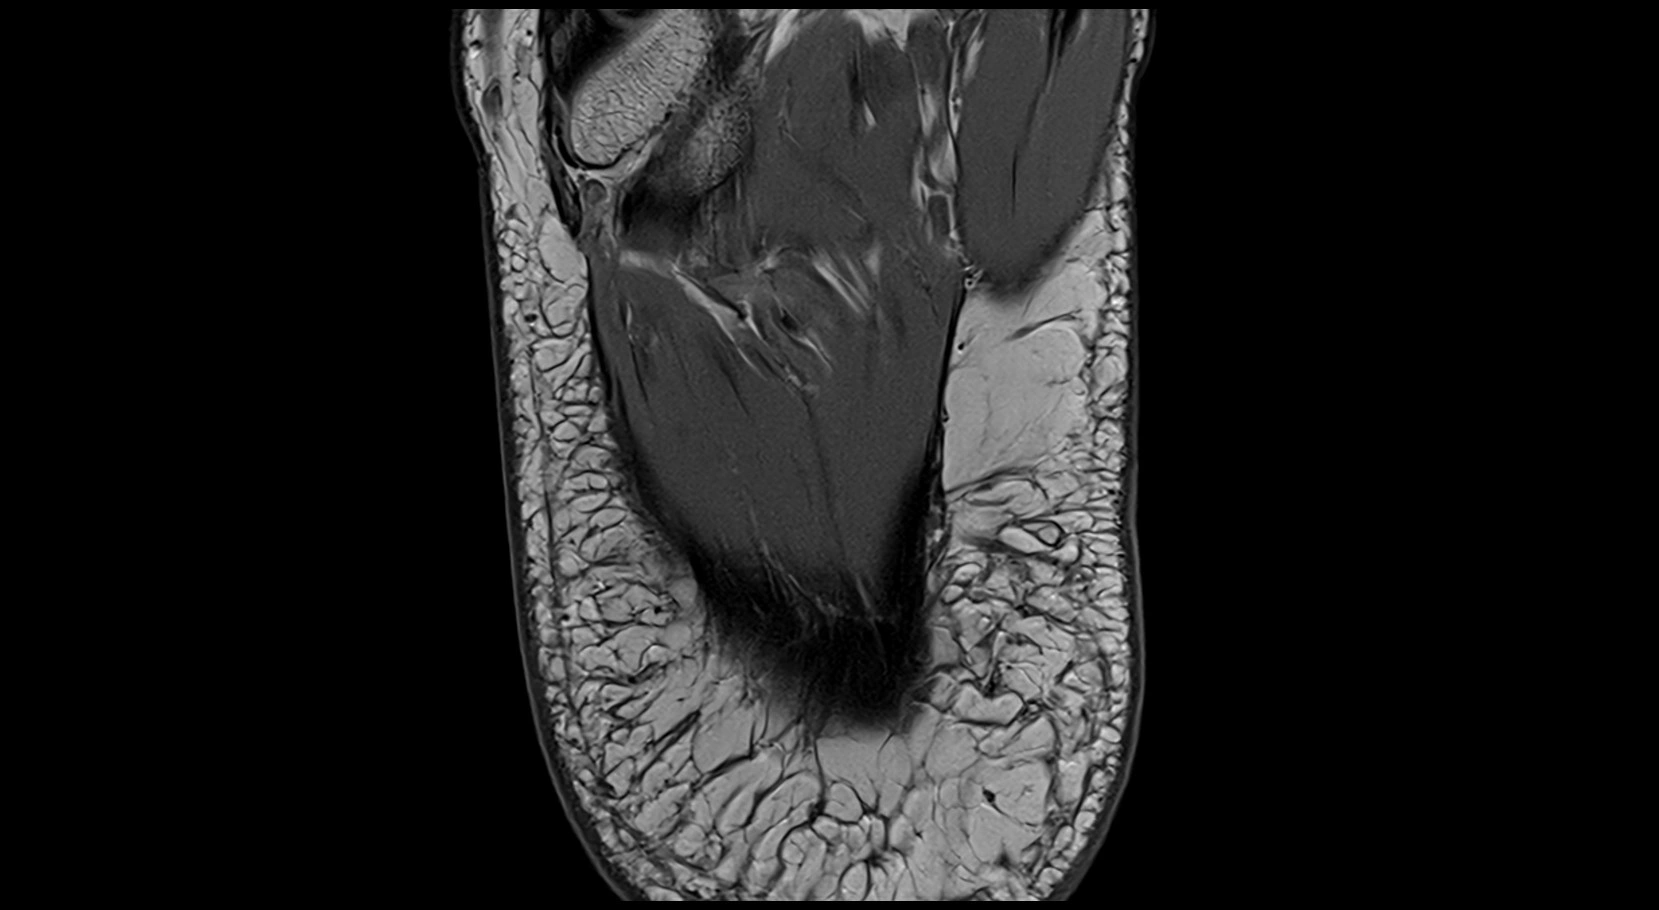

MRI image

image